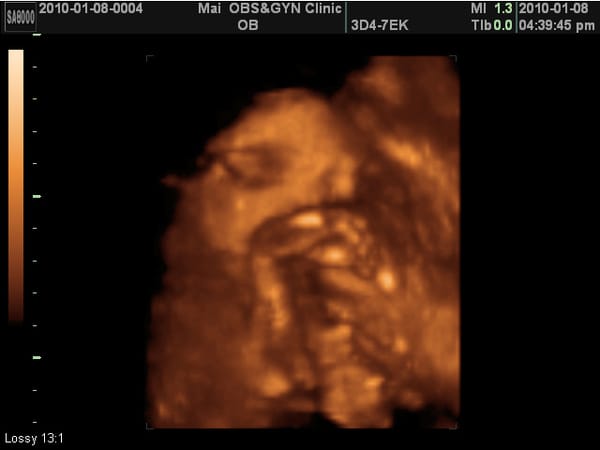

30W第六次產檢

醫生說看起來像媽媽,像嗎? 我覺得臉胖胖的,鼻子扁扁的,嘴巴厚厚的耶~ 傅說:哪個小孩子不是長這樣?     小老虎第六次產檢,驗尿ok,血壓ok,母親體重64.5KG。 小老虎上次產檢913公克,這次1500多,這四周又胖了1.3KG,還OK。 血壓:94/47 頭28w,稍小。 小老虎的頭原本在我的右側,這次滾到左側來了,這一個月間她翻轉了一百八十度,難怪我的肚子老被她拿 […]…